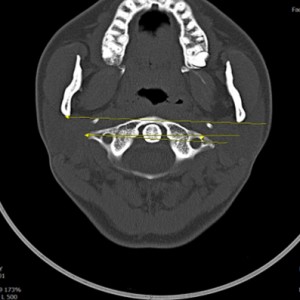

안면 두개골 CT

경추 1,2번의 변위 파악

턱의 소리가 오래되지 않아서 근육의 긴장만 있는 경우 치료 후 소리의 감소가 빠른 편이나 인대의 문제일 경우 턱의 위치를 교정후 인대를 강화하는 치료를 추가적으로 해서 더 줄일수 있습니다. 디스크가 닳아버린 문제라면 치료후에도 소리가 남을수 있습니다. CT와 초음파등의 영상진단을 통해 치료 예후와 경과를 확인 가능합니다.

턱관절 검사에 전신 척추를 촬영·검사하는 이유가 무엇인가요?

턱관절과 척추가 신체 정렬과 기능에 밀접하게 연결되어 있기 때문입니다. 턱관절 문제는 목뼈를 포함한 척추 정렬에 영향을 미치며, 이는 전신적인 불균형을 초래할 수 있습니다. 또한 턱관절과 척추는 근육 및 신경계를 통해 상호작용하므로, 턱관절 이상은 목과 어깨는 물론 척추 전체에도 연쇄적인 영향을 미칠 가능성이 있습니다. 전신 척추 촬영은 턱관절 문제의 정확한 원인을 파악하고, 자세와 정렬의 이상을 분석하여 근본적인 치료 전략을 세우기 위해 필수적입니다.